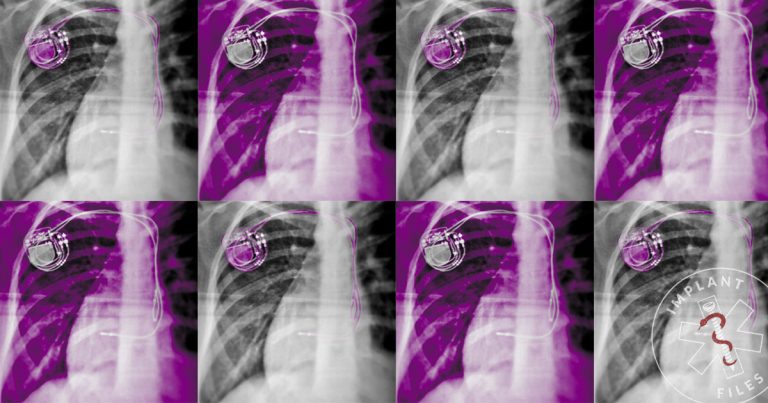

Por dentro do cartel dos implantes